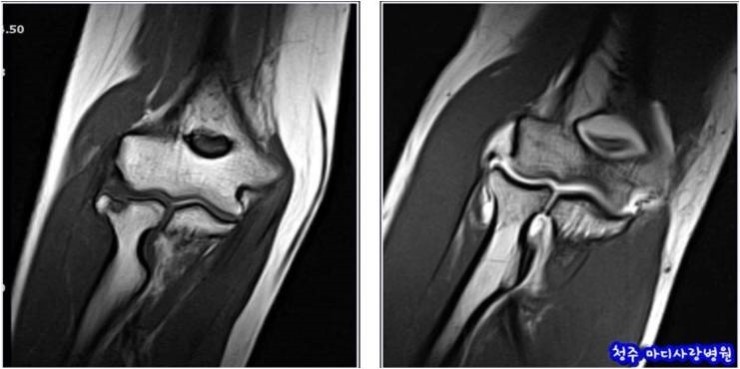

MRI(자기 공명 영상)은 강력한 자기장과 라디오파를 이용하여 체내 조직의 이미지를 생성하는 기술입니다. MRI는 연부 조직, 즉 뇌, spinal cord, 근육, 그리고 다양한 내장 장기 등을 상세하게 볼 수 있는 특징이 있습니다. 주로 신경계, 근골격계 및 종양 연구의 진단 도구로 사용됩니다.

MRI는 인체 내의 수소 원자의 자기적 성질을 이용하여 이미지를 생성합니다. 강력한 자기장이 수소 원자를 정렬시킨 후, 라디오 파를 통해 이들을 자극하여 방출되는 신호를 수집합니다. 수집된 신호는 컴퓨터에 의해 해석되어 이미지를 만들어 내는데, 이 과정에서 세부적인 이미지가 생성되어 체내 구조를 명확하게 볼 수 있게 됩니다.

- 연부 조직을 상세히 분석할 수 있다.

- 종양의 크기와 위치를 정확히 파악할 수 있다.

- 신경계의 문제를 진단하는 데 효과적이다.

MRI는 종종 다음과 같은 경우에 사용됩니다.

- 신경계 문제(뇌종양, 뇌졸중 등)의 진단

- 근골격계 질환(관절염, 연골 손상 등)의 평가

- 복부 및 흉부 장기의 비정상적인 상태 파악